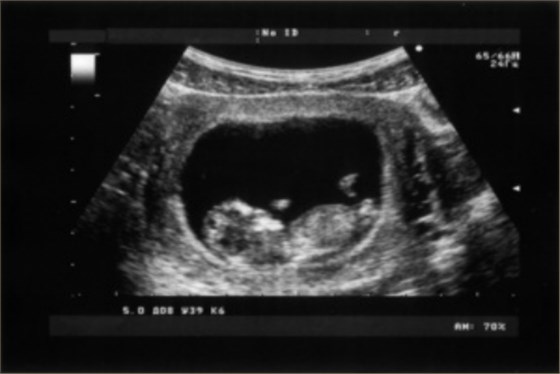

孕期超聲檢查,是為了檢查胎兒在子宮內(nèi)的發(fā)育情況,包括胎兒的頭部、四肢、各個臟器、神經(jīng)系統(tǒng)、消化系統(tǒng)、泌尿系統(tǒng)等。孕期超聲檢查單會有胎心監(jiān)護、胎兒的附屬物、胎盤、羊水等項目,一般是看三維彩超、四維彩超、胎兒的臍帶和胎盤情況。

孕期超聲檢查能夠及時了解胎兒在子宮內(nèi)的發(fā)育情況,是孕期較為重要的檢查項目。在孕期除了要定期產(chǎn)檢以外,還需要增加對身體的營養(yǎng)補充,有利于胎兒的生長發(fā)育。